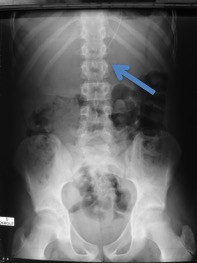

catheter pelotonné - introduction du cathéter sous contrôle de la vue

- ne pas raccourcir le catheter : il ne peut pas être trop long, mais il peut devenir trop court

- après avoir vérifié le fonctionnement de la valve, et pratiquée des fentes sur les 10 derniers cm.